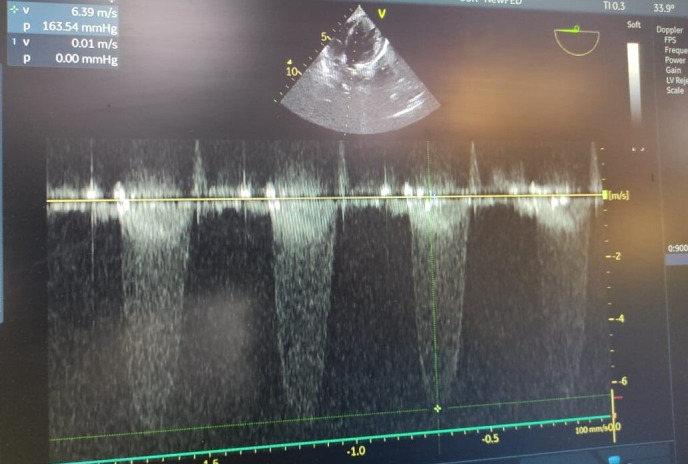

Background. The microbial infection of the endocardium, popularly known as Infective Endocarditis (IE), is typically classified on the basis of anatomy, valve nativity and its associated microbiology. As per the associated microbiology, Staphylococcus aureus is the most common microorganism responsible for the cause of IE. Even though, the Streptococcus group accounts for a smaller percentage of IE, however this doesn't give us the liberty of ignoring the high mortality and morbidity associated with this pathogen. Case presentation. We report an unusual case of neonatal sepsis, complicated with endocarditis, caused by penicillin resistant Streptococcus parasanguinis . The neonate however died of the same despite all efforts. The said baby was given birth by a mother with gestational diabetes mellitus.